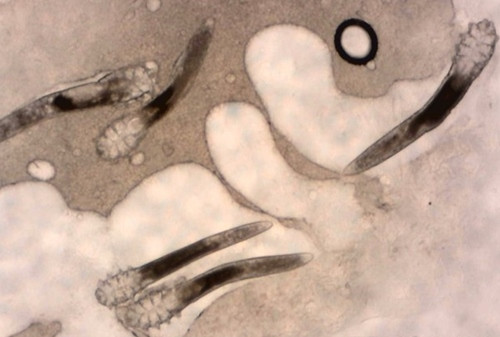

Vậy mạt demodex là gì? Demodex gồm đầu thân đuôi và 8 chân gần phần đầu với vòng đời: 14 – 24 ngày. Chu kỳ sống của nó có 5 giai đoạn: trứng, ấu trùng, tiền nhộng, nhộng và con trưởng thành.

![]() |

| Ký sinh trùng Demodex khiến bệnh viêm da nặng hơn. |

Demodex thường sống thành cặp, sau khi giao cấu, vi khuẩn trên da mặt đi sâu vào bên trong da và đẻ trứng ở vị trí nang lông hoặc tuyến bã, mang theo vi khuẩn và bài tiết ra chất thải, chết ở trong da ngay sau khi đẻ trứng.

Sau khi chết, xác của chúng hóa lỏng và phân hủy trên bề mặt da, và gây ra phản ứng dị ứng ở một số bộ phận của các mô da, đốm đỏ (mụn trứng cá) xảy ra tình trạng viêm da dị ứng tại chỗ, ban đỏ, ban sẩn và mụn mủ. Đây đều là phản ứng bởi hệ thống miễn dịch.